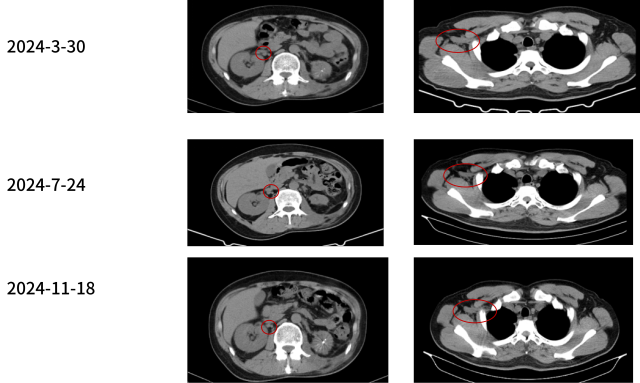

病情变化:疾病进展

2024-3-30

临床诊断

左肾透明细胞癌伴肉瘤样分化 TxN1M1 IV 期

双肺转移 纵膈、右肺门淋巴结转移 腹腔转移 右侧肾上腺转移

肌肉转移 后腹膜转移 骨转移 脑转移

诊疗经过-3

2024-04-

三线:伏罗尼布+依维莫司

治疗结局:影像学评估 SD